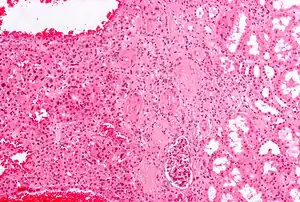

An oncocytoma is an epithelial tumor composed of oncocytes, large eosinophilic cells having small, round, benign-appearing nuclei with large nucleoli and excessive amounts of mitochondria.

In gross appearance, the tumors are tan or mahogany brown, well circumscribed and contain a central scar. They may achieve a large size (up to 12 cm in diameter).

The main differential diagnosis of renal oncocytoma is chromophobe renal cell carcinoma oncocytic variant, which like the renal oncocytoma has eosinophilic cytoplasm, but has perinuclear clearing and, typically, some degree of nuclear atypia.

Micrograph of a renal oncocytoma. H&E stain.